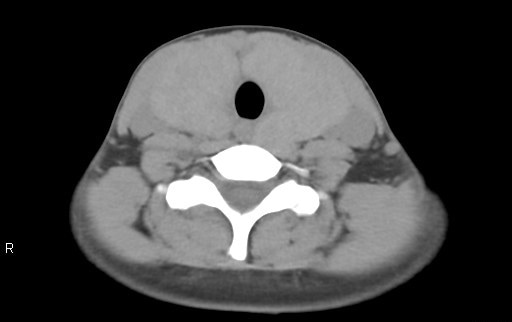

当院では、CTAや金属アーチファクトの低減、また甲状腺の容量測定のオーダーが出た場合にDual Energyにて撮影をしています。特に甲状腺の容量測定時は低keV画像を利用して容量測定を行っています。

下記症例は19歳女性、甲状腺摘出術前で甲状腺容量測定の依頼があり、従来のCT装置では、Dual Energy撮影が出来なかったため、管電圧120kVで撮影していましたが、甲状腺の辺縁が同定しにくく、辺縁をトレースするのに苦労していました。Revolution CTが導入され、Dual Energy撮影が可能となり、低keVの画像を使用することで、甲状腺のCT値が上昇し境界が明瞭になり、容量測定が容易になりました。

70keV